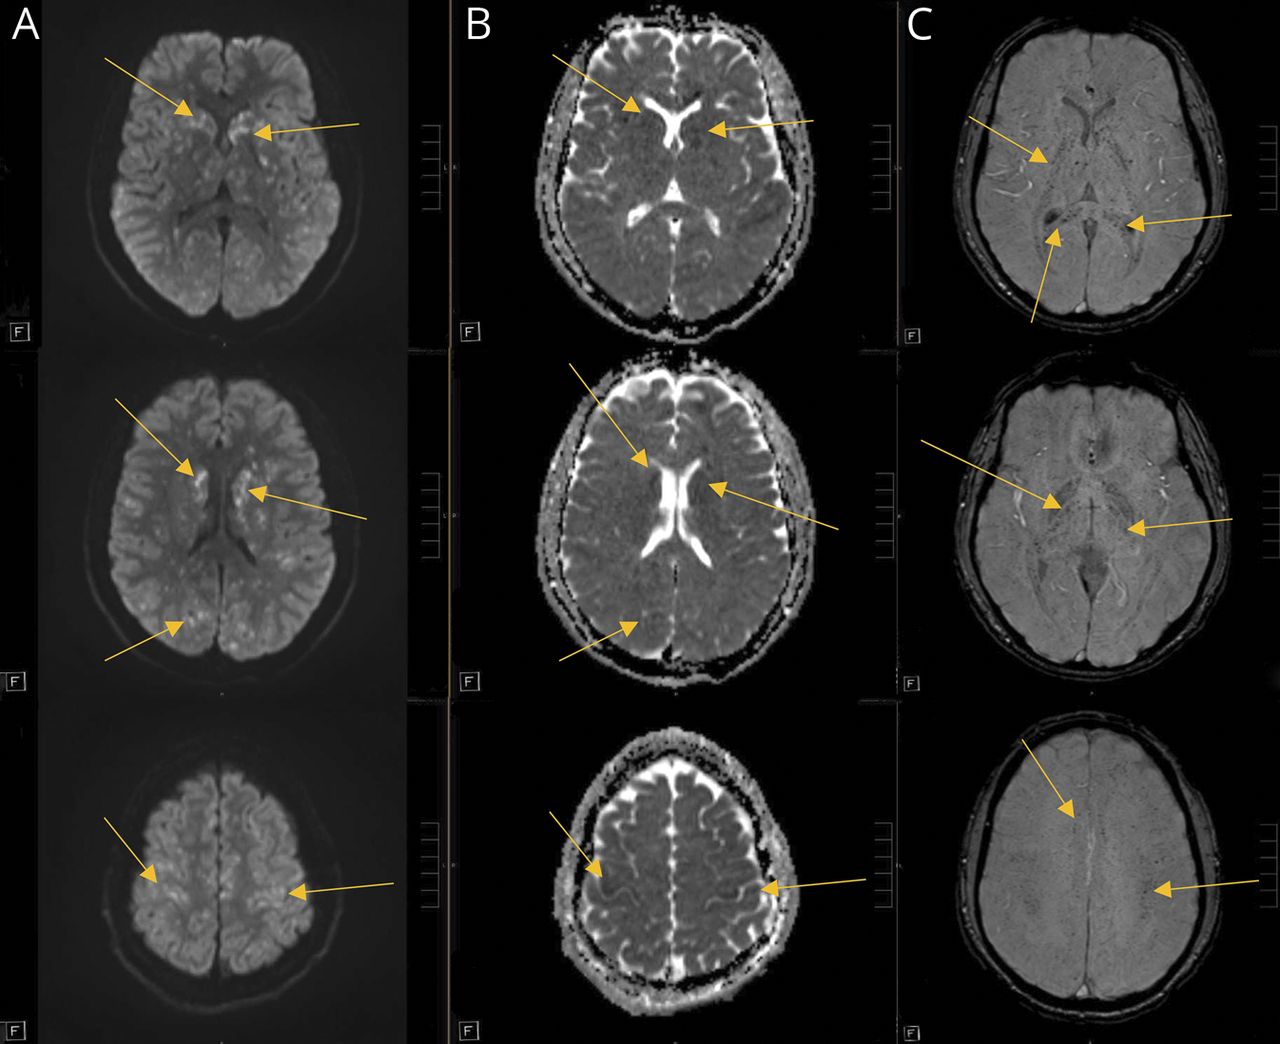

符合最初的本地化双边半球,MRI大脑没有对比postfall第一天显示广泛的证据bihemispheric受伤,广泛地分散点状的疫源地的扩散限制(图1)和大量的证据bihemispheric microhemorrhages (图2)。

(Diffusion-weighted成像hypertintensities驾车,)和表观扩散系数序列hypointensities (ADC, B)显示弥漫性点状的疫源地的扩散限制,与susceptibility-weighted成像hypointensities显示许多microhemorrhages(瑞士,C)。

MRI发现点状的疫源地的限制扩散和microhemorrhages建议过程涉及小血管、鉴别诊断包括血管炎,microangiopathic流程或栓子的原因。血管炎似乎不太可能,考虑到严重的时间进程。没有裂细胞外围涂片显示血栓性血小板减少性紫癜或弥散性血管内凝血。非常小的模式与扩散斑点状的microhemorrhages梗塞是符合心脏栓子,通常会导致更大的梗塞和没有bihemispheric microhemorrhages。技术超声心动图显示没有栓塞或卵圆孔未闭的心脏内的来源。Four-limb静脉双深静脉血栓形成的研究显示没有证据。